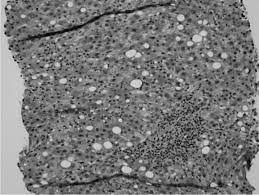

Fluoxetine Induced Stevens Johnson Syndrome And Liver Injury Agrawal 2019 Journal Of Clinical Pharmacy And Therapeutics Wiley Online Library

Fluoxetine Induced Stevens Johnson Syndrome And Liver Injury Agrawal 2019 Journal Of Clinical Pharmacy And Therapeutics Wiley Online Library from onlinelibrary.wiley.com